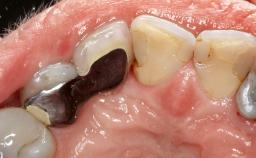

Due to their promising clinical performance, zirconia implants have recently become popular alternatives to titanium implants, particularly for areas with high esthetic demands (Holländer and coworkers 2016; Roehling and coworkers 2016; Lorenz and coworkers 2019). However, regardless of the reported high survival and success rates, zirconia implants were affected by peri-implant diseases over the short observation period, suggesting the importance of treating peri-implant diseases at zirconia implants (Becker and coworkers 2017). In their case, Frank Schwarz and Ausra Ramanauskaite present 3-year results following mechanical debridement alongside Er:YAG laser monotherapy.